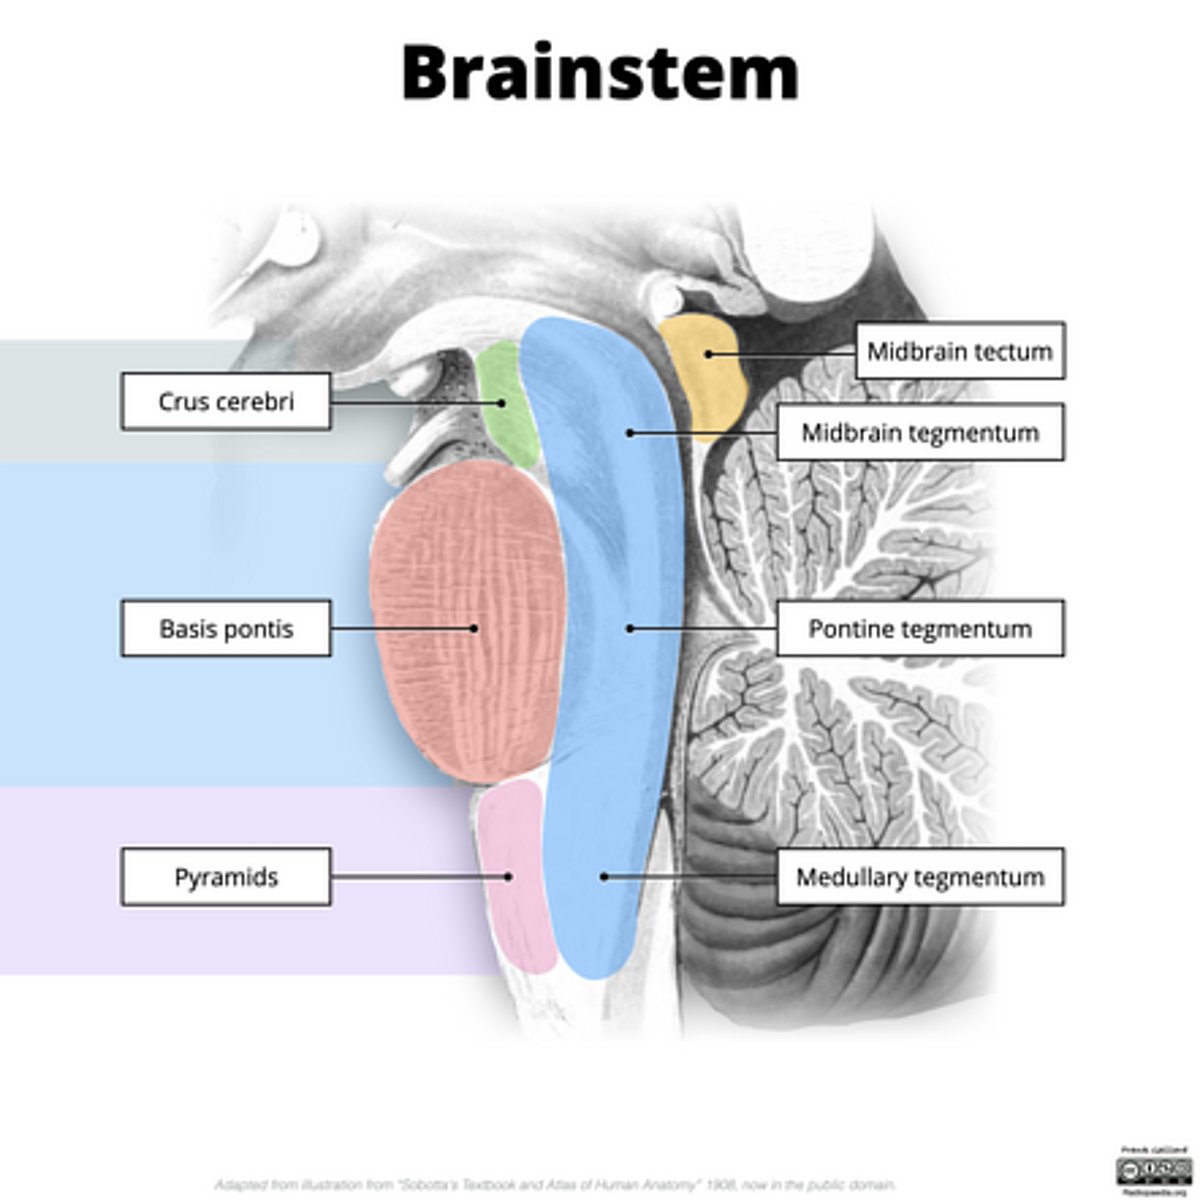

What are the structures of the brainstem?

1. mesencephalon (midbrain)

2. pons

3. medulla oblongata

What is the tectum?

roof of the midbrain

What is the tegmentum?

floor of midbrain

What are the fibers of the tegmentum?

ascending fibers

What is the crus cerebri?

part of the cerebral peduncles which contain descending tracts

What are the fibers of the crus cerebri?

descending fibers

image -- 5